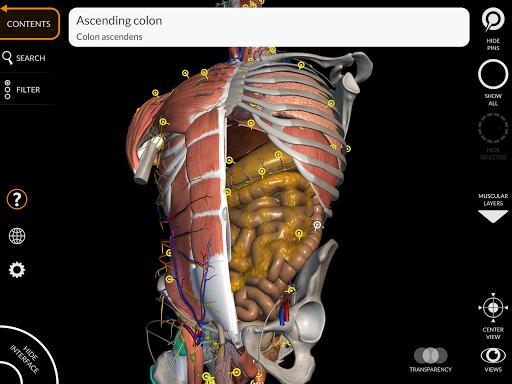

Поділ за регіонами та попередньо визначені види полегшують спостереження та вивчення окремих частин або груп систем і зв’язків між різними органами.

• Травна система

• Можливість приховування або ізоляції однієї чи кількох вибраних моделей

• Фільтр, щоб приховати або відобразити кожну систему

• Функція пошуку, щоб легко знайти кожну анатомічну частину

• Вибравши модель або шпильку, з’явиться відповідний анатомічний термін

• Травна система